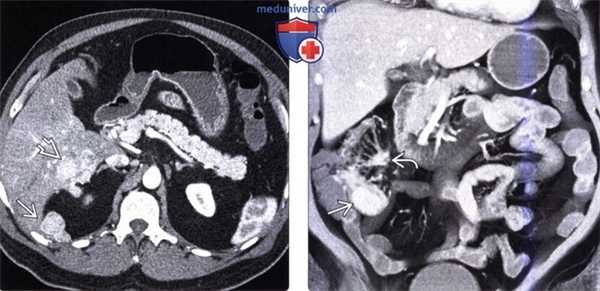

(Слева) На аксиальной КТ с контрастным усилением у мужчины 75 лет определяется в значительной степени васкуляризованное образование в желудочно-печеночной связке, непосредственно примыкающее к малой кривизне желудка.

(Справа) На корональной КТ с контрастным усилением (объемный рендеринг) у этого же пациента отчетливо определяется, что это образование вплотную прилежит к стенке желудка. При исследовании резектата было обнаружено, что образование является экзофитной карциноидной опухолью желудка. Кроме того, подобный внешний вид может иметь ГИСО желудка.

Нейроэндокринная опухоль (НЭО) желудка G1 (карциноидные опухоли) у пациента с гипергастринемией.

(а, б) Выявлены два гиперденсивных полиповидных образования: по малой кривизне в верхней части тела желудка (а, стрелка) и по задней стенке тела желудка (б, стрелка).

Образование в верхней части тела желудка (а) имеет центральное изъязвление. Нейроэндокринная опухоль (НЭО) желудка G2 и нейроэндокринная карцинома (мелкоклеточный тип).

(а) При КТ в коронарной проекции в антральном отделе желудка визуализированы гиперденсивное полиповидное образование (белая стрелка) и пораженный метастазом регионарный лимфатический узел (черный указатель), который имеет внутреннюю зону некроза и гиперденсивную солидную часть.

При патоморфологическом исследовании, проведенном после гастрэктомии, был установлен диагноз НЭО желудка II степени с метастазированием в регионарный лимфатический узел.

(б) При КТ в коронарной проекции выявлена язвенно-рибовидная опухоль (стрелка), расположенная по большой кривизне тела желудка; в правой доле печени обнаружены два гиперденсивных образования (указатели).

Установлено, что это образование представляет собой нейроэндокринную мелколкеточную карциному с метастазированием в печень.